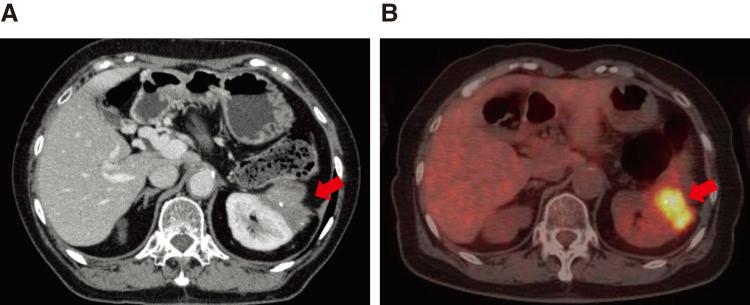

The patient was a 69-year-old woman with a pancreatic tumor that was detected with computed tomography (CT) during a postoperative colon cancer checkup. She was suspected of having pancreatic body cancer without distant metastasis. Distal pancreatectomy with celiac axis resection was performed. Postoperative pathological examination revealed an invasive ductal adenocarcinoma with lymph node metastasis (pT4N1M0, stage III). Postoperatively, she received adjuvant chemotherapy containing gemcitabine and S-1 for 1 year and 4 months, and S-1 monotherapy for 1 year. Six years and 2 months after the initial surgery, her serum carbohydrate antigen 19-9 level elevated, and CT revealed soft tissue in front of the left kidney. Positron emission tomography/CT also revealed high fluorine-18 fluorodeoxyglucose uptake in the tissue. Accordingly, the patient was diagnosed with dissemination of PDAC. The patient was administered chemotherapy with gemcitabine and S-1. One year and 6 months after the diagnosis of dissemination, CT revealed reduction of the nodule. Therefore, we decided to eliminate this dissemination. A left nephrectomy and partial gastrectomy were performed. Histopathological examination confirmed dissemination of PDAC. The patient refused adjuvant chemotherapy. No evidence of recurrence has been observed for 13 years and 3 months since the initial surgery, and 5 years and 1 month since the resection of the dissemination.

该患者为一名69岁女性,在结肠癌术后检查时通过计算机断层扫描(CT)发现胰腺肿瘤。怀疑患有胰体癌且无远处转移。进行了伴有腹腔干切除的远端胰腺切除术。术后病理检查显示为浸润性导管腺癌伴淋巴结转移(pT4N1M0,Ⅲ期)。术后,她接受了含吉西他滨和S-1的辅助化疗1年零4个月,以及S-1单药治疗1年。初次手术后6年零2个月,她的血清糖类抗原19-9水平升高,CT显示左肾前方有软组织。正电子发射断层扫描/CT也显示该组织中氟-18氟脱氧葡萄糖摄取高。因此,该患者被诊断为PDAC播散。给予患者吉西他滨和S-1化疗。播散诊断后1年零6个月,CT显示结节缩小。因此,我们决定切除这种播散灶。进行了左肾切除术和部分胃切除术。组织病理学检查证实为PDAC播散。患者拒绝辅助化疗。自初次手术以来13年零3个月,以及自播散灶切除以来5年零1个月,均未观察到复发迹象。